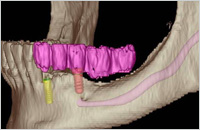

In besonderen Fällen nutzen wir die digitale Volumentomographie (DVT) bzw. die Computertomographie (CT), um mit dreidimensionalen Aufnahmen des knöchernen Gesichtsschädels schon vor einem Eingriff das Knochenangebot, die Knochenqualität und individuelle Besonderheiten zu erkennen. Mit den gestochen scharfen 3-D-Ansichten können wir die knöchernen Strukturen des Oberkiefers und des Unterkiefers, ausgesuchte, einzelne Segmente oder komplexe Zusammenhänge detailliert darstellen. Diese neue Technik eröffnet uns zuverlässige diagnostische und therapeutische Möglichkeiten in der Implantologie, Prothetik, Kieferorthopädie und Zahnerhaltung.